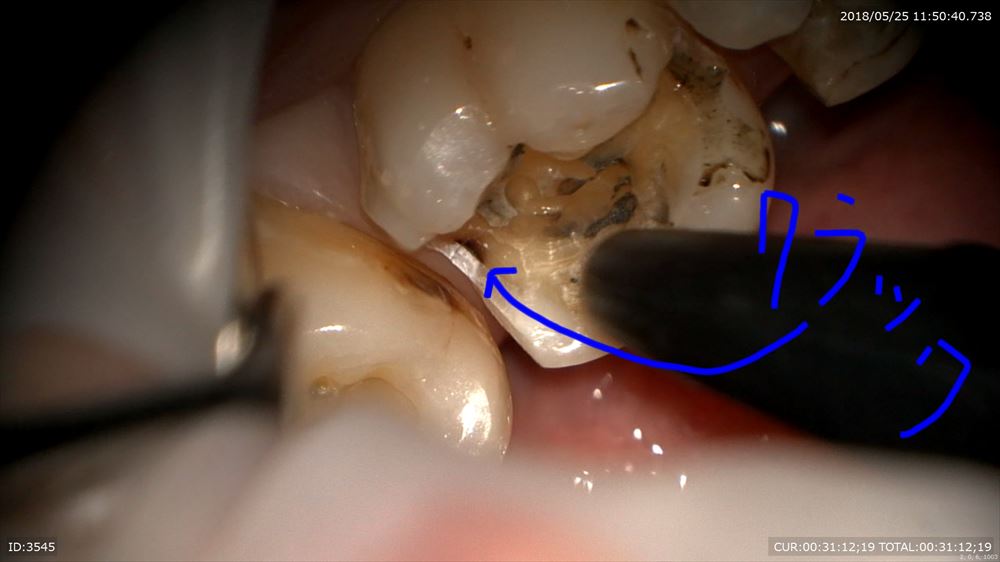

咬むと痛いときはヒビやクラックが原因という事が多いです。金属の下の虫歯だけでなく

ここを拡大。クラック見てみましょう。20倍

この様に虫歯はクラックからも発生します。